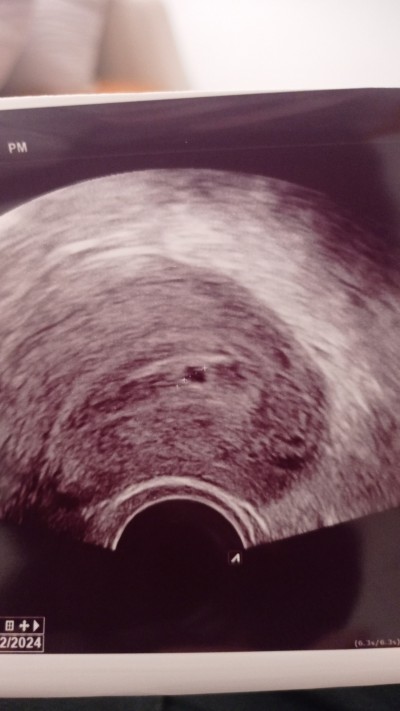

Benımde bugün gıttım

image